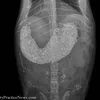

Terkadang beberapa hewan bisa saja menelan hal-hal yang tidak terduga. Hal tersebut bisa diakibatkan ketidaktahuan dari hewan itu sendiri, atau memang hewan tersebut memiliki kelainan makan.

Kami memiliki beberapa foto tentang benda-benda aneh yang pernah masuk ke dalam perut hewan. Apa saja? Simak deh.